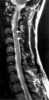

Acute myelitis

Transverse myelitis (TM) is a rare neurological condition in which the spinal cord is inflamed. Transverse implies that the inflammation extends horizontally across the spinal cord. [Source: Wikipedia ]